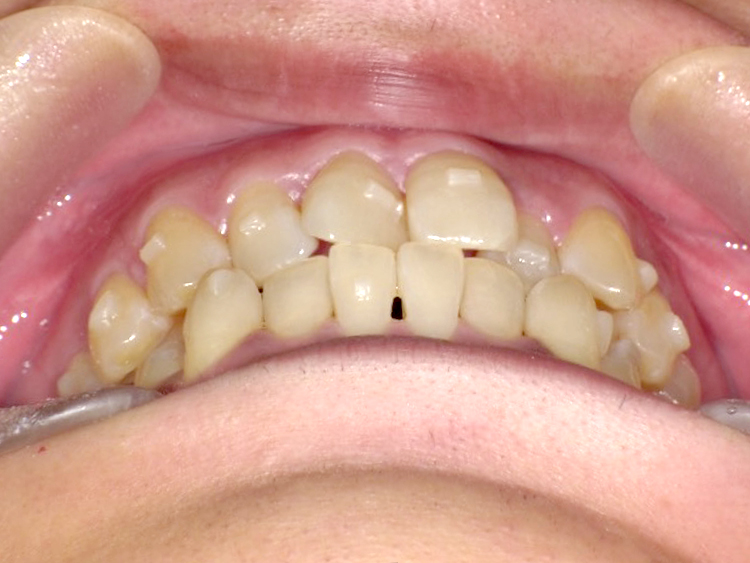

症例2

Before

After

| 主訴 | 上前歯のガタガタを治したい |

|---|---|

| 年齢 | --- |

| 治療期間 | 約1年 |

| 治療内容 | インビザラインiGoで上顎のみ治療。 プチ矯正では前から3番目の歯は動かせないが、 この治療では動かすことができるので、 気になる箇所を綺麗に並べることができた。 |

| 治療費 | ¥352,000(税込)+月額調整料 |

| 治療のリスク | 歯と歯の間を削ることでスペースを確保するので、 場合によっては歯が染みる症状が出ることがある。 |